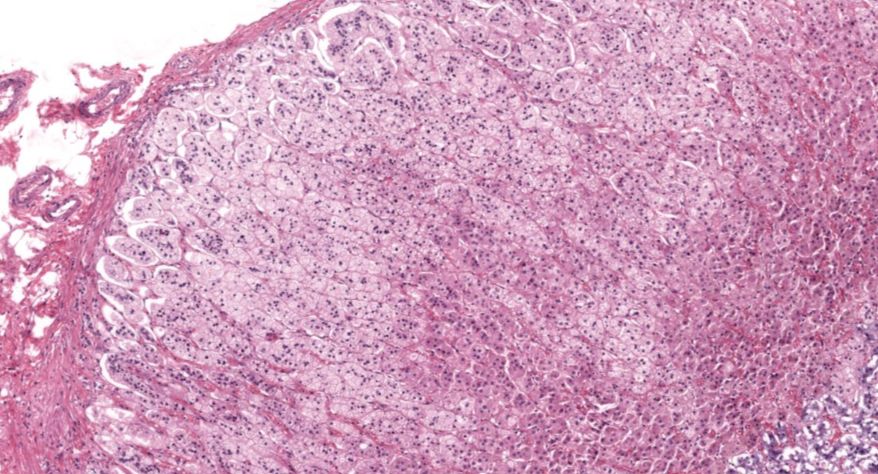

低倍镜观察:1. 被膜:由薄层结缔组织组成。2. 实质:由许多大小不等的滤泡构成。滤泡壁是单层立方上皮细胞,滤泡腔内充满粉红色匀质胶状物,滤泡之间的结缔组织内有丰富的血管。高倍镜观察:1. 滤泡:滤泡壁的单层滤泡上皮细胞一般呈低柱状或立方状,胞质着浅色,细胞核呈圆形。滤泡腔内充满了粉红色匀质胶质。2. 滤泡旁细胞:体积较大,呈圆形或椭圆形;细胞核较大,呈圆形,着色较浅,细胞质染色也较浅。细胞或嵌在滤泡壁上或成团分布于滤泡之间。3. 间质:由结缔组织组成。位于滤泡之间。其中含有丰富的毛细血管及三五成群的滤泡旁细胞。

3.滤泡上皮细胞

4.胶质